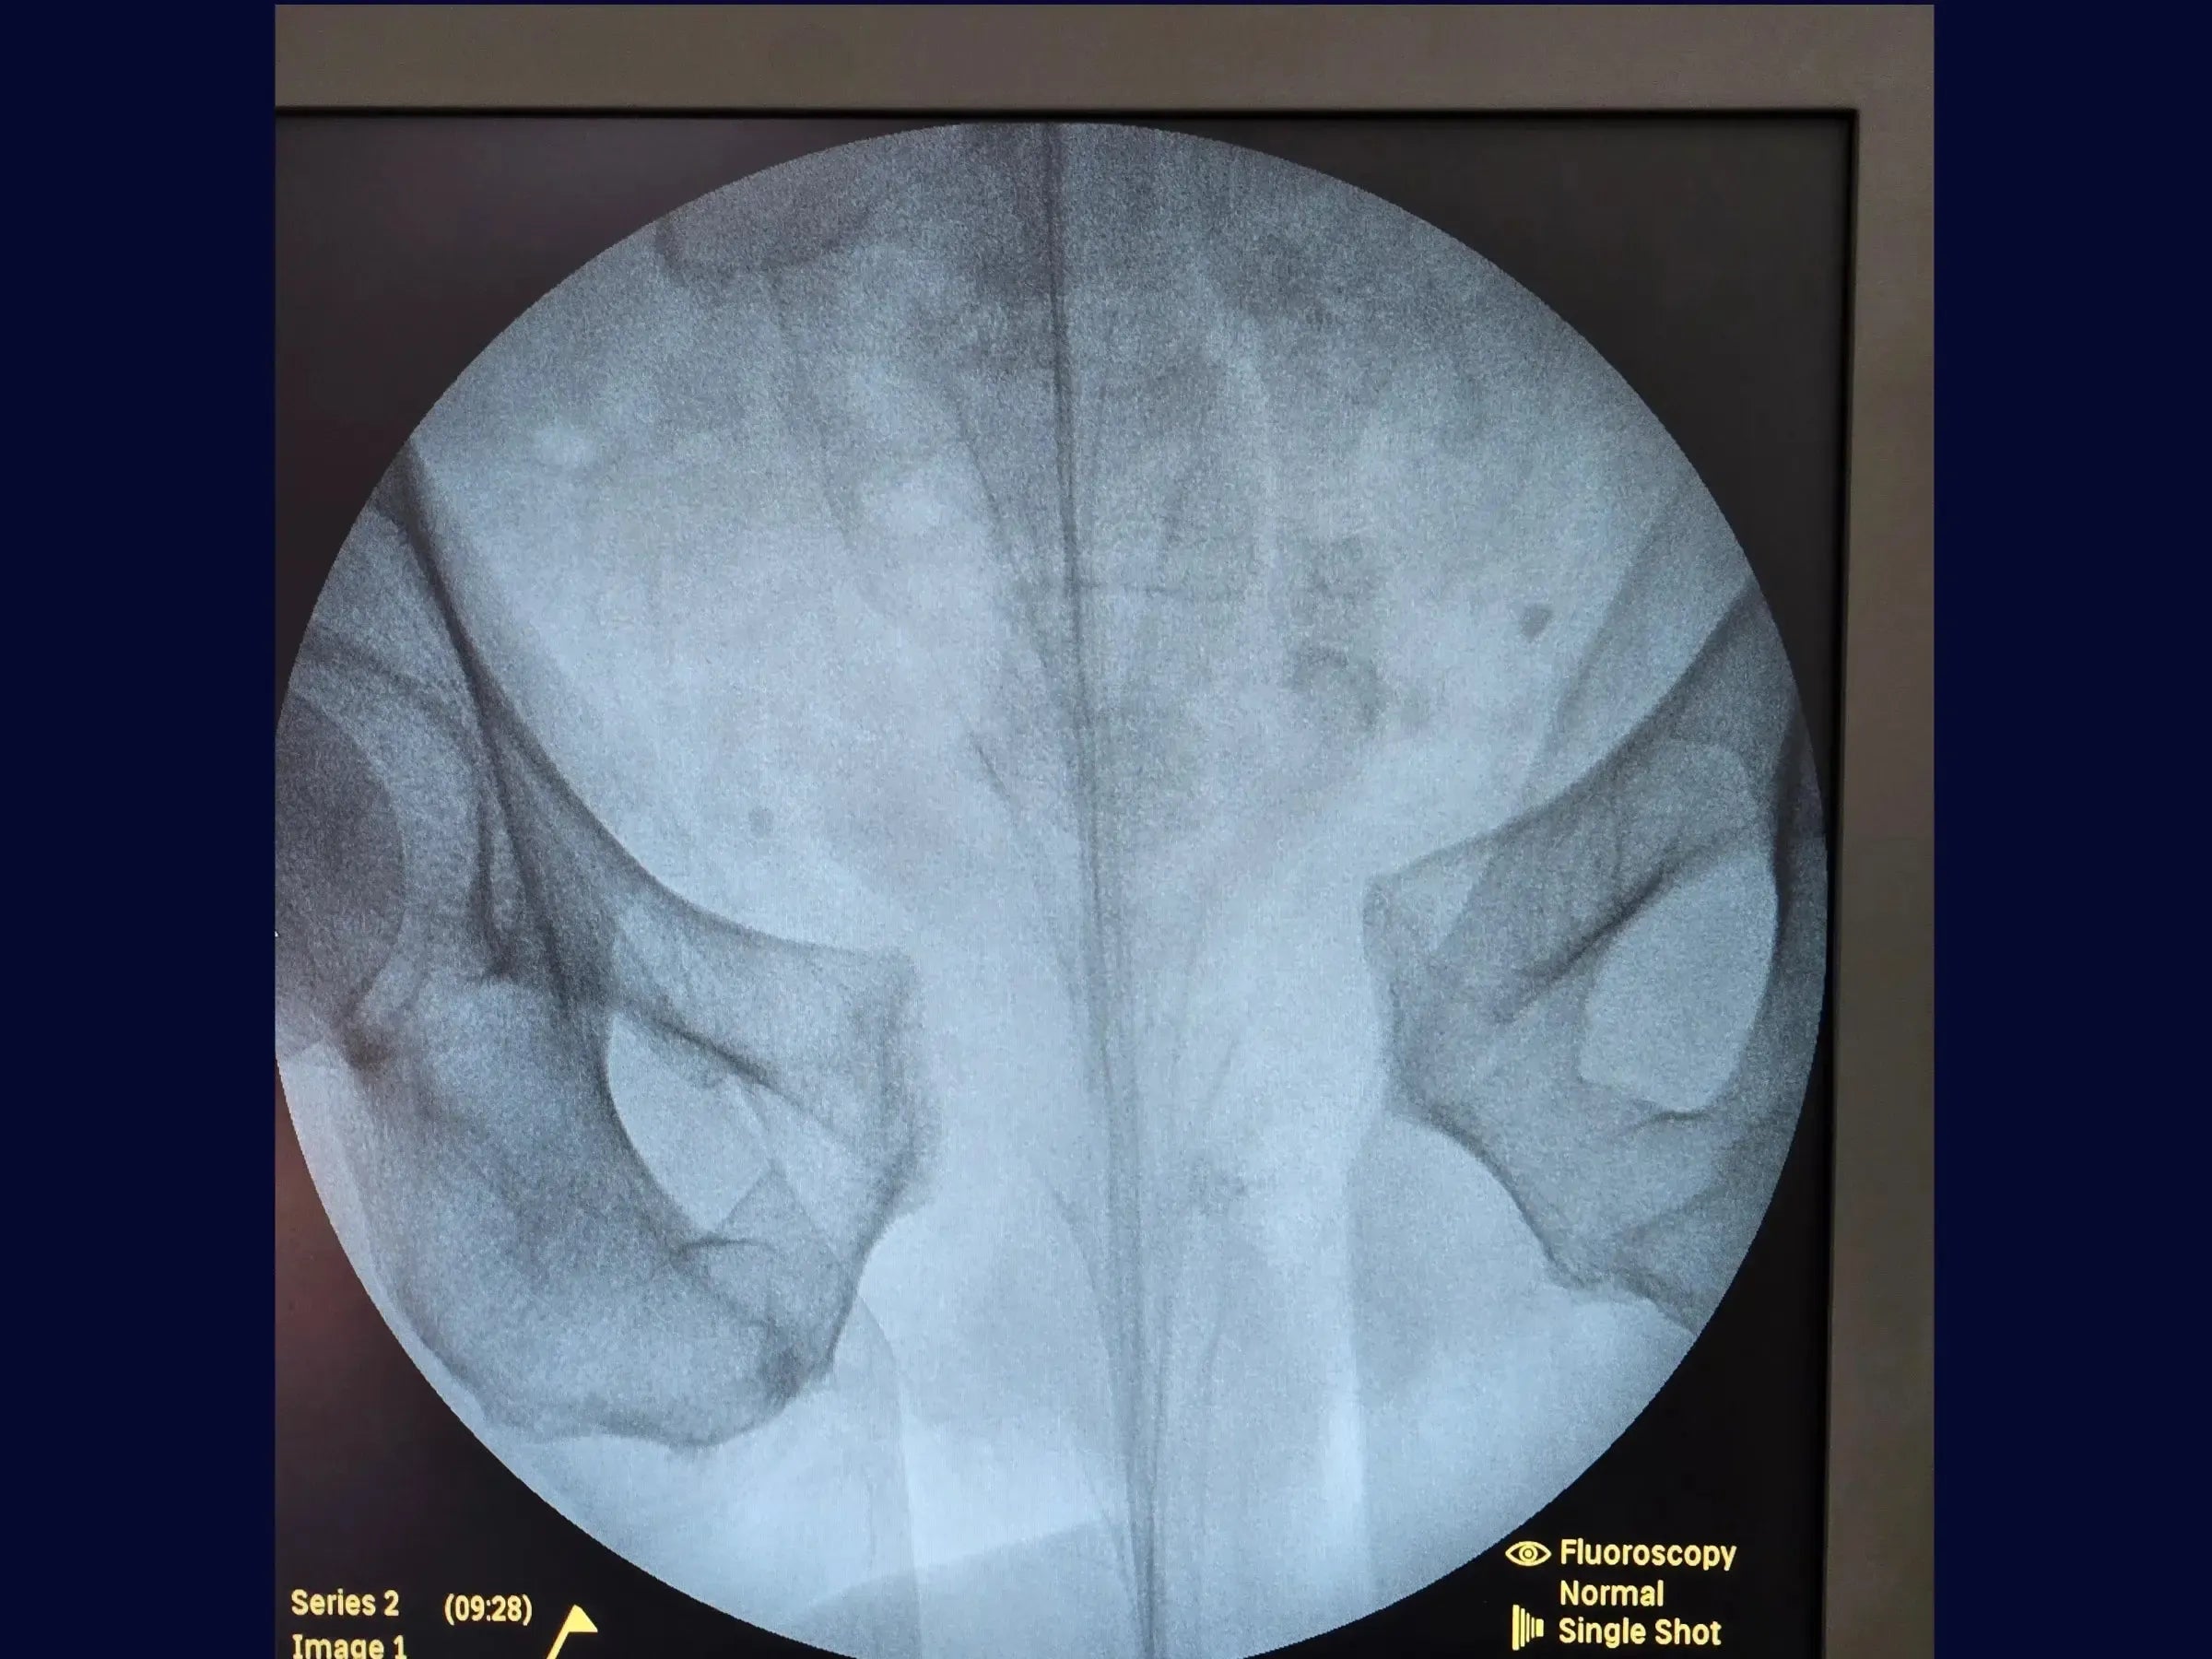

Lesão do Anel Pélvico "Open Book" (Luxação da Sínfise Púbica)

Domine o tratamento cirúrgico da lesão do anel pélvico do tipo "open book", uma abertura da sínfise púbica. Este treinamento oferece uma imersão prática na redução e fixação anterior, abordando desde o posicionamento do paciente e o acesso cirúrgico, com atenção à bexiga, até a utilização de parafusos temporários para redução controlada e a aplicação de placas para fixação definitiva, visando a estabilidade do anel pélvico e a reabilitação precoce.

- Tratamento de lesão do anel pélvico "open book" (luxação da sínfise púbica).